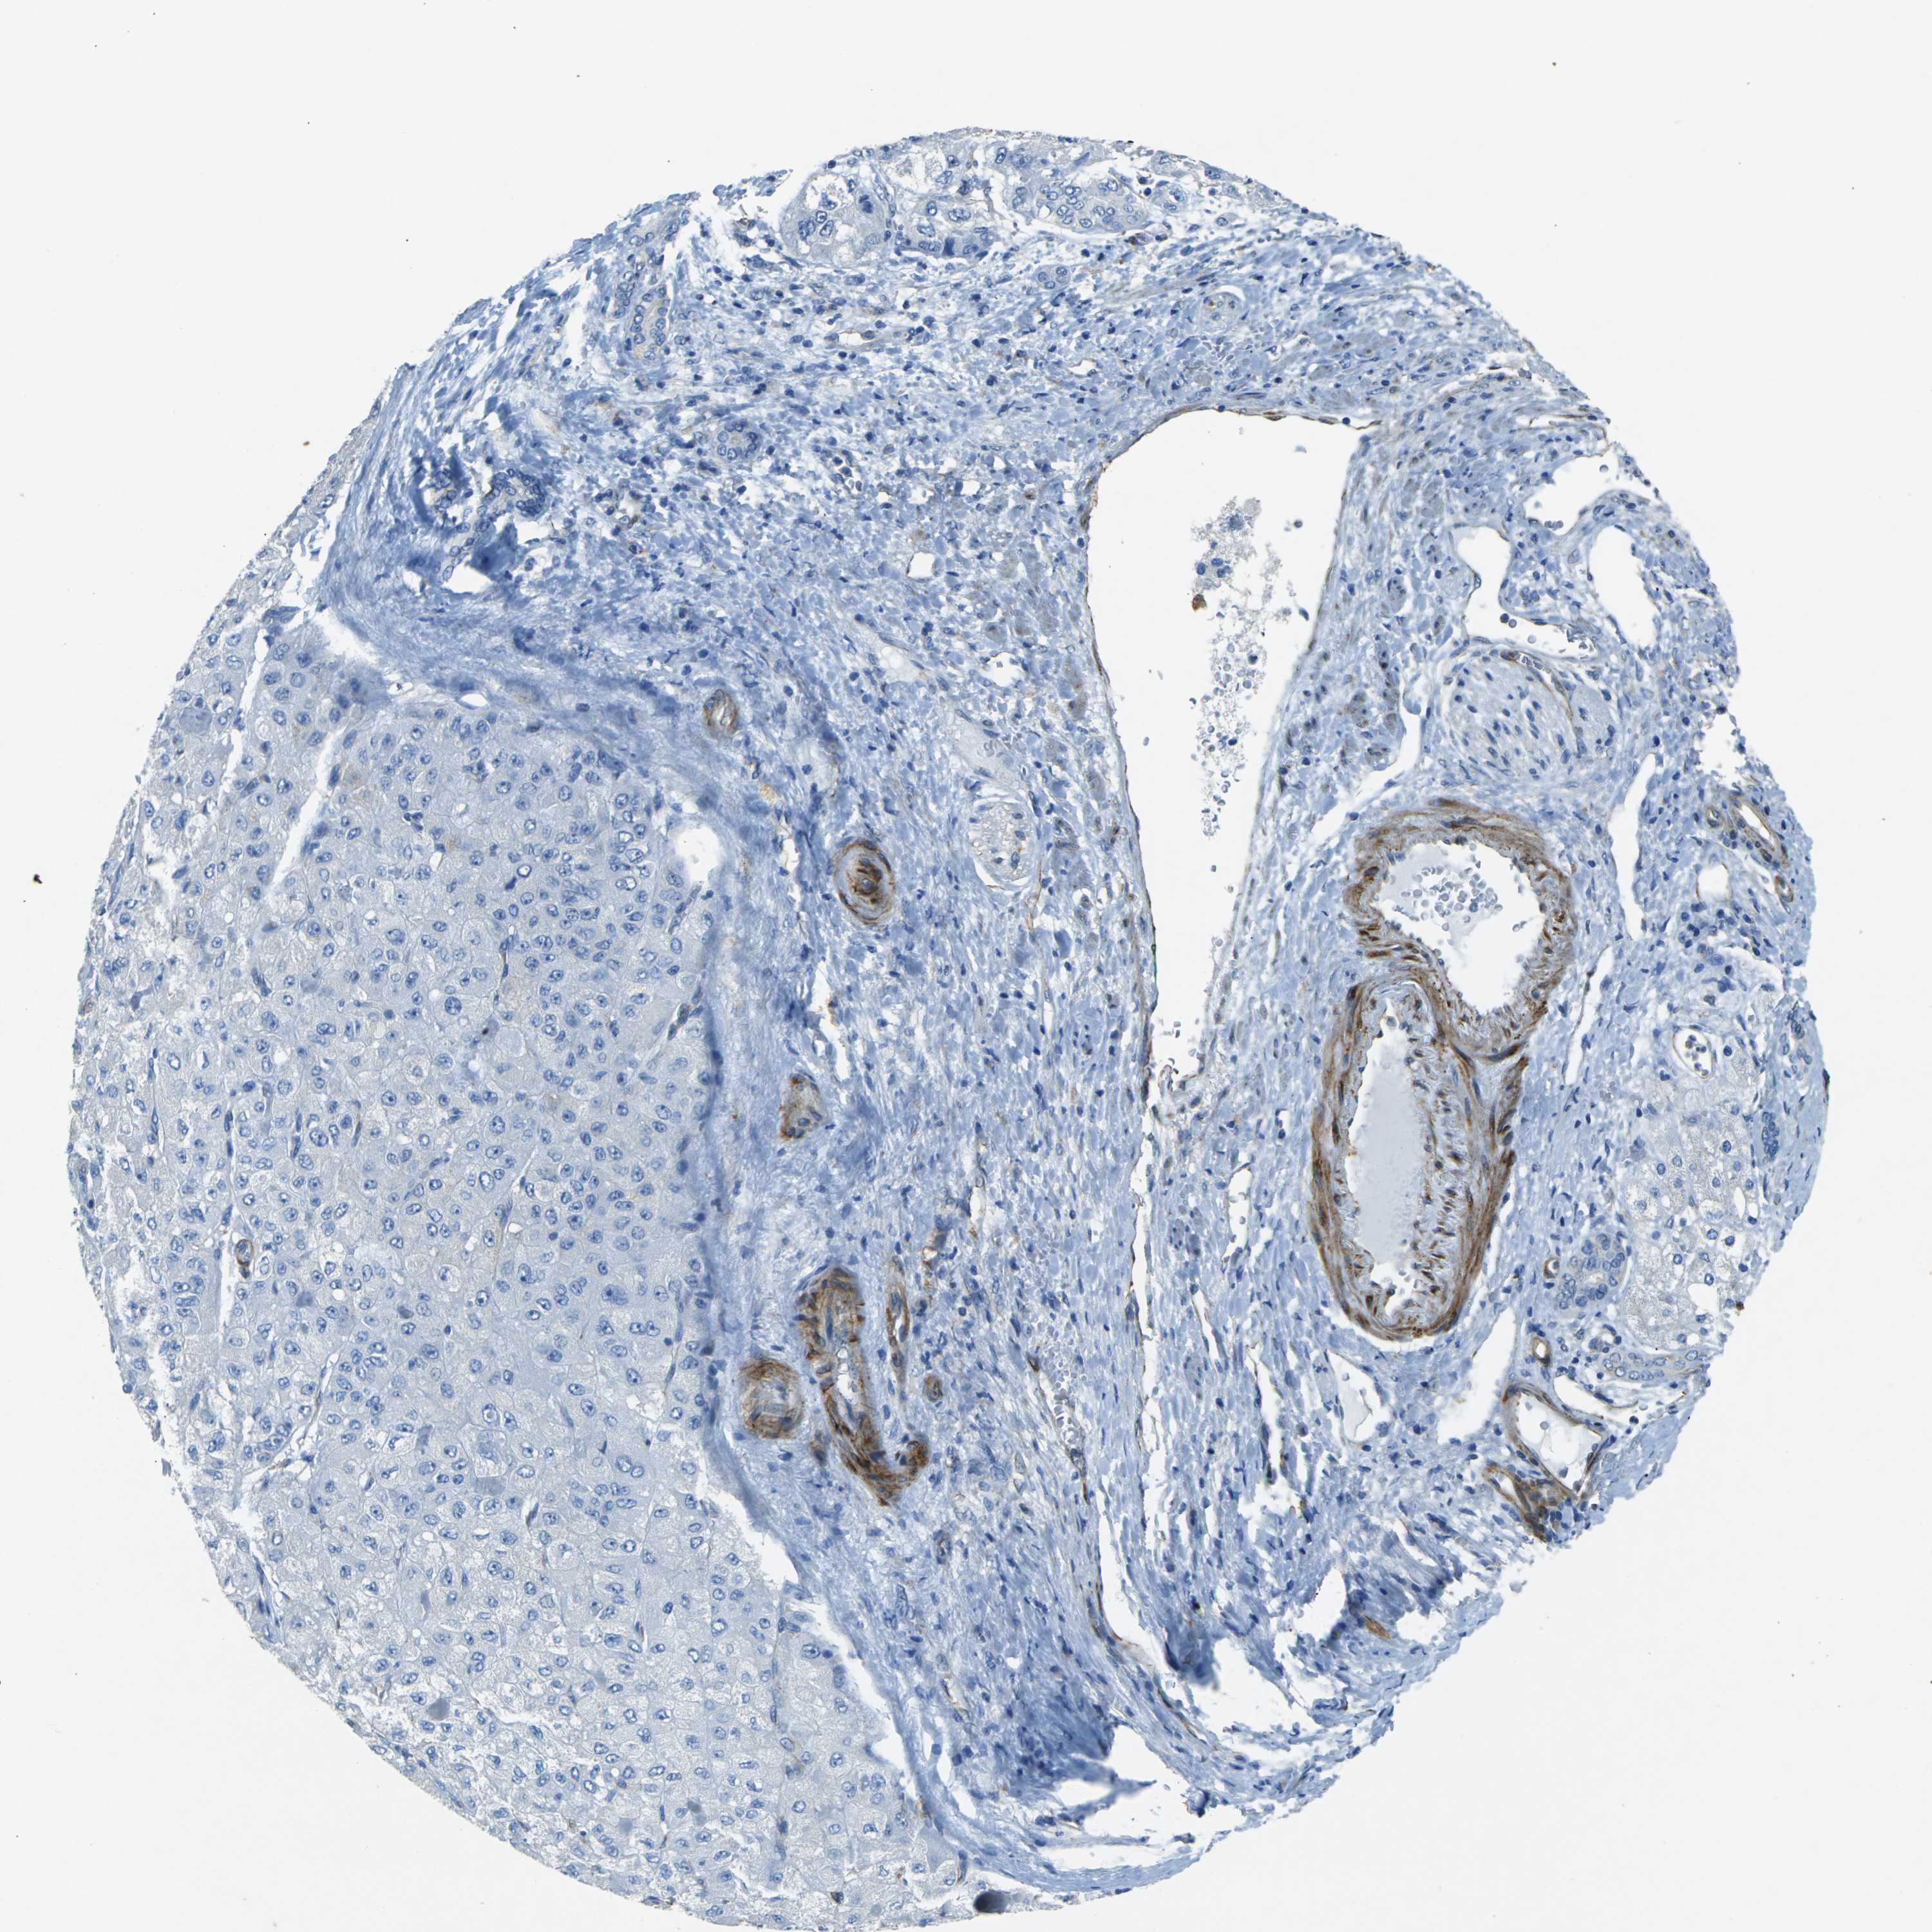

LIVER CANCER - Protein expressioni

A mouse-over function shows sample information and annotation data. Click on an image to view it in a full screen mode. Samples can be filtered based on level of antibody staining by selecting one or several of the following categories: high, medium, low and not detected. The assay and annotation is described here.

Note that samples used for immunohistochemistry by the Human Protein Atlas do not correspond to samples in the TCGA dataset.

Antibody stainingi

Antibody staining in the annotated cell types in the current human tissue is reported as not detected, low, medium, or high, based on conventional immunohistochemistry profiling in selected tissues. This score is based on the combination of the staining intensity and fraction of stained cells.

Each image is clickable and will lead to virtual microscopy that enables deeper exploration of all samples and also displays staining intensity scores, fraction scores and subcellular localization as well as patient and tissue information for each sample.

Antibody HPA006889

Antibody CAB011498

Staining

High

Medium

Low

Not detected

Intensity

Strong

Moderate

Weak

Negative

Quantity

>75%

75%-25%

<25%

None

Location

Nuclear

Cytoplasmic/membranous

Cytoplasmic/membranous,nuclear

Cholangiocarcinoma

Carcinoma, Hepatocellular, NOS